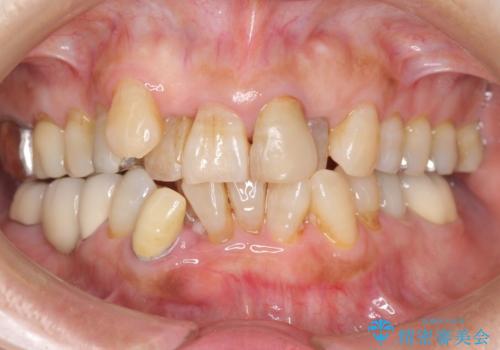

親知らずの移植 4年半経過症例 70代女性

- 親知らずの移植治療から4年半経過した患者様です。

他の歯の治療をご希望され、数年ぶりに来院して下さいました。

移植した親知らずは全く問題ないそうで、「まるで自分の歯のようです。本当にすごい技術ですね。」とおっしゃって下さいました。

歯肉の腫脹や退縮、動揺も認められませんでした。

4年半前に行った自家歯牙移植に大変ご満足頂き、ご家族も紹介して下さいました。